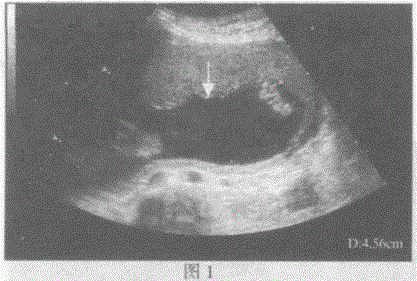

问题 请指出下图箭头间所指的是宫内妊娠哪一部位:

选项 A.图1:胎盘厚度图2:羊水深度 B.图1:羊水深度图2:胎盘厚度 C.图1:胎儿双顶径图2:胎儿腹围 D.图1:胎儿股骨长径图2:胎儿股骨长径

答案 B